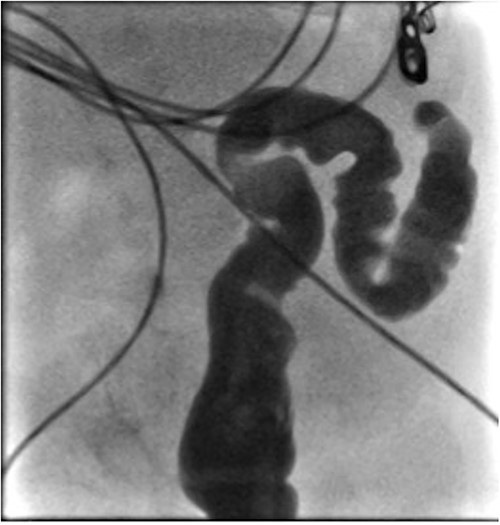

At elective ileostomy closure 2 months later, a colonic stricture was found 5 cm distal to mucous fistula, which was resected. Saline was instilled distal to the excised colonic stricture, which did not progress suggesting further distal obstruction. The decision was made to defer stoma closure at this stage. Subsequent colonoscopy revealed normal distal colon up to the level of the distal transverse colon at which point the colon was completely occluded in a blind ending pouch and on probing with a guide wire no lumen was found. Atresia was confirmed with contrast enema (Fig. 3). At 8 months of age, he underwent laparotomy and resection of a 10 cm section of transverse colonic atresia. Histology reported narrowing of the transverse colon, focal granulation tissue, and mucosal web formation. His recovery and subsequent follow-up have been uneventful.

Contrast enema for case 2 showing complete failure of passage of contrast into distal transverse colon.